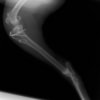

ミニチュアダックスフンド 9歳 未去勢♂

突然の非負重性の右後肢跛行を主訴に来院されました。触診上、右膝の伸展痛が認められ、整形外科学的検査において右膝の内外側の膝蓋骨脱臼(Grade Ⅱ)、脛骨圧迫テストで陽性が認められました。神経学的検査において特に異常は認められませんでした。レントゲン検査において、関節液の貯留所見や脛骨の前方変位の所見は認められませんでいた。

関節穿刺を行い、好中球はなく、少数のマクロファージや滑膜細胞が認められるました。膝蓋骨脱臼および前十字靭帯断裂による退行性の関節炎を疑い、関節鏡検査を実施いたしました。関節鏡検査では、重度の滑膜炎および前十字靭帯の完全断裂が認められました。内外側とも半月板に損傷は認められませんでした。

■ 外科的治療法

断裂前十字靭帯の除去を行いました。外側方向からのテンションが著しく、外側広筋と膝関節外側支帯の解放を行いました。膝関節伸展機構の著しいアライメント異常が認められたため、脛骨粗面転移術を実施しました。

写真の膝関節の垂直線を綿棒の木柄が表しており、遠位の脛骨粗面との位置関係が平行ではありません。

転移側の骨床は犬種特有の変形した表面であったため、転移後の骨片の圧着状態が改善するように変形表面をラウンドバーにて切削しました。滑車溝の著しい低形成が認められたため、滑車溝形成術を実施いたしました。

切断された関節包の縫縮を行いました。前十字靭帯断裂後の不安定性と内旋を解消するために、人工靭帯(fiber wire)によるラテラルスーチャー法を併用し安定化を図りました。

術後、整形外科学的検査における脛骨圧迫テストや前方引き出し兆候は認められませんでした。